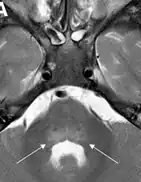

Common features included acute focal limb weakness and specific findings on magnetic resonance imaging (MRI) of the spinal cord consisting of nonenhancing lesions largely restricted to the grey matter. In most cases, these lesions spanned more than one level of the spinal cord. Some also had acute cranial nerve dysfunction with correlating nonenhancing brainstem lesions on MRI. None of the children experienced altered mental status or seizures. None had any cortical, subcortical, basal ganglial, or thalamic lesions on MRI. Most children reported a febrile respiratory illness in the two weeks preceding development of neurologic symptoms. In most cases, cerebrospinal fluid (CSF) analyses demonstrated mild-moderate pleocytosis (increased cell count in the CSF) consistent with an inflammatory or infectious process.

The three cases since August really look like each other. They have severe arm flaccidity and no mental status changes. All of them have similar spine MRIs showing gray-matter involvement. You could lay all three MRIs on top of each other and they look almost the same. It's pretty striking. ... It you lift the arm up, it literally drops. Sensation is usually intact. There might be slightly decreased sensation in the other arm, but these are younger kids, so they're not always so cooperative in giving you a good sensory exam.[29]

Children's Mercy Hospital, which had three or four cases in 2014, reported that the MRI images and symptoms closely mimicked polio. They reported: "The sudden onset of flaccid paralysis in single or multiple limbs with absolutely no sensory findings, the MRIs all showing uniformly a signal increase in the ventral horns of the spinal cord — this is exactly the same region of the spinal cord affected in polio ... Almost all of the patients have an increase in their white blood cells in the cerebrospinal fluid. Some of the patients have brainstem findings and cranial-nerve findings."[29]